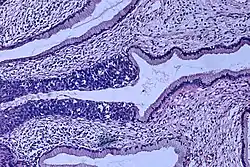

The naming and histologic classification of cervical carcinoma precursor lesions has changed many times over the 20th century. The World Health Organization classification system was descriptive of the lesions, naming them mild, moderate, or severe dysplasia or carcinoma in situ (CIS).[68][69] The term cervical intraepithelial neoplasia (CIN) was developed to place emphasis on the spectrum of abnormality in these lesions and to help standardize treatment.[69] For premalignant dysplastic changes, cervical intraepithelial neoplasia grading (CIN 1–3) is used. It classifies mild dysplasia as CIN1, moderate dysplasia as CIN2, and severe dysplasia and CIS as CIN3.[70] More recently, CIN2 and CIN3 have been combined into CIN2/3. These results are what a pathologist might report from a biopsy.